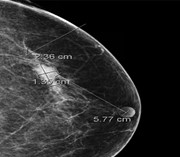

Synchronous presentation of invasive ductal carcinoma and mantle cell lymphoma: a diagnostic challenge in menopausal patients

Edward J. Woo and others

Journal of Surgical Case Reports, Volume 2016, Issue 1, January 2016, rjv153, https://doi.org/10.1093/jscr/rjv153